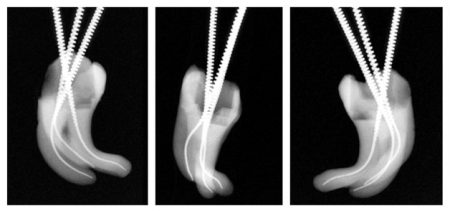

- Пломбирование гуттаперчей – обеспечивает максимально плотное заполнение зубных каналов, для повышения качества фиксации пломбировочного материала. Метод актуален при пломбировании широких каналов жевательных зубов;

- Метод вертикальной конденсации – термопластичная гуттаперча вводится в полость инъекционным путем.